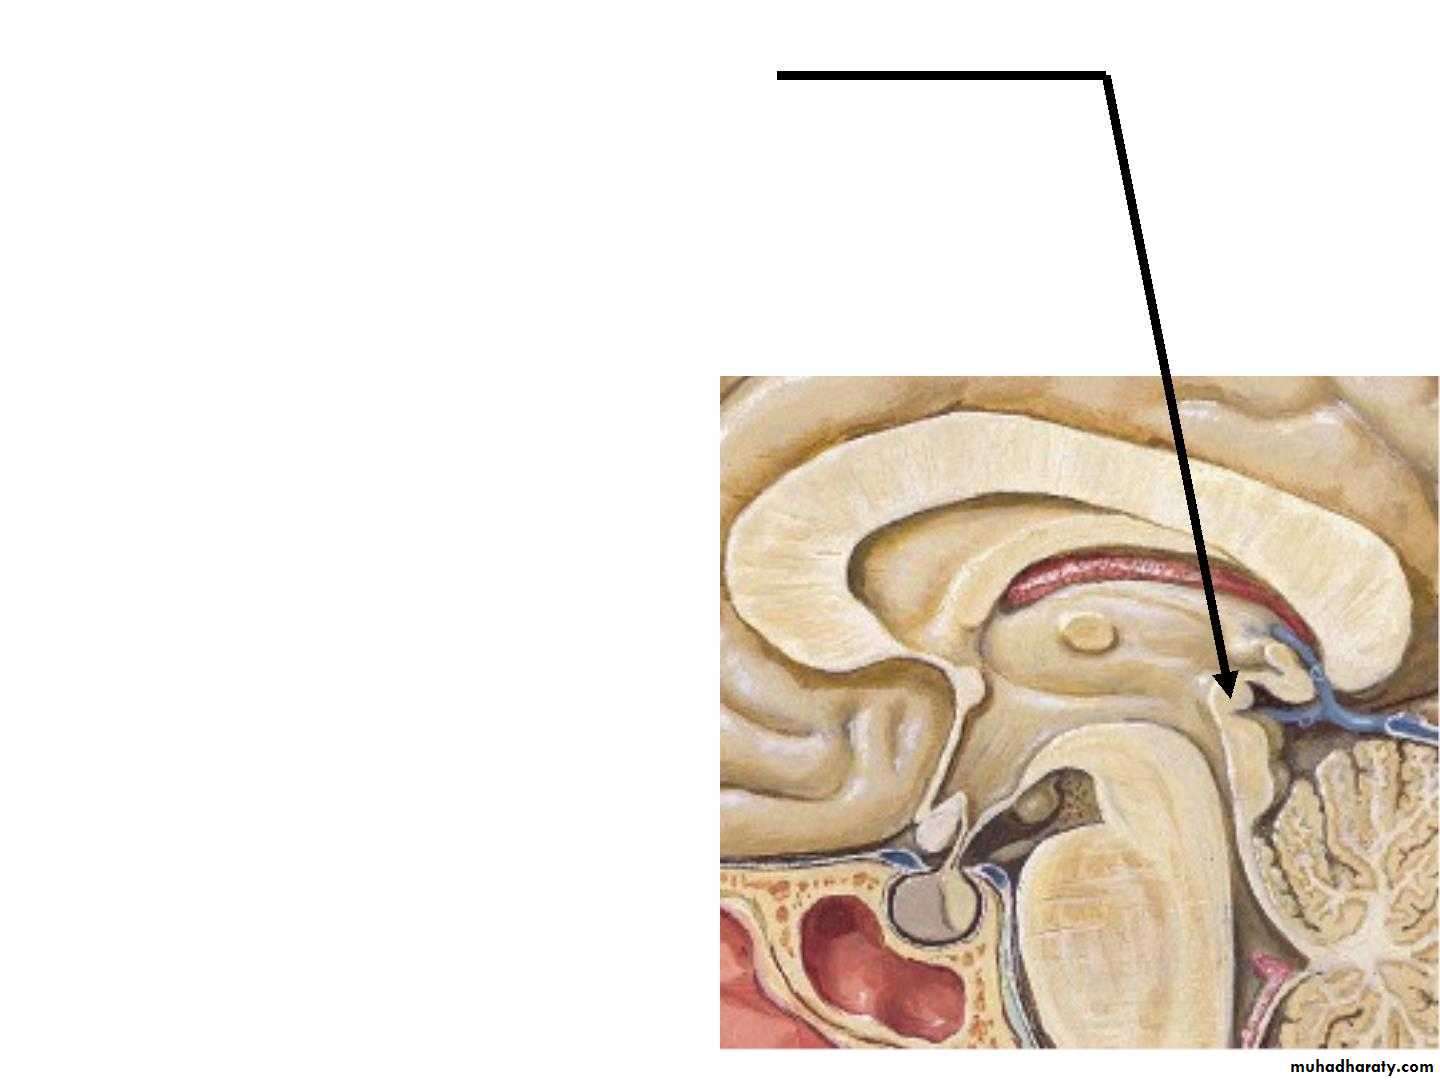

• A. Corpus callosum:

• •• the largest commissure of

• the brain,

• • connects the two cerebral

• hemispheres.

• •

• It lies at the bottom of the

• longitudinal fissure.

• • it is divided into :

• 1. Rostrum :

is a thin part of anterior end of corpus callosum which is prolonged posteriorly to be continuous with upper

end of the lamina terminalis.

• 2. Genu :

is the curved anterior end of the corpus callosum that bends inferiorly in front of the septum pellucidum.• 3. Body :

• Arches posteriorly and ends as

4. splenium

• B. The anterior commissure :

• is a small bundle of nerve fibers that crosses the midline in the lamina terminalis.• C.Posterior Commissure :

Is a bundle of nerve fibers that crosses the midline immediately above the opening of the cerebral aqueduct into the third ventricle.• Fornix